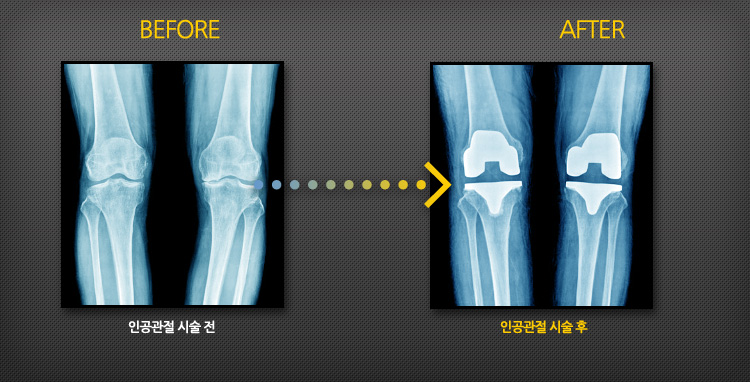

인공 슬(무릎)관절 치환술 증례

인공 슬(무릎)관절 치환술의 효과!

수술 후 대부분 관절의 통증이 없어지고, 완벽하지는 않지만 보행, 계단 오르내리기, 가벼운 운동 등의 일상생활을 무리 없이 할 수 있습니다. 인공관절의 수명은 대개 15~20년이며, 근래에는 점차적으로 기구의 수명이 연장되고 있습니다.